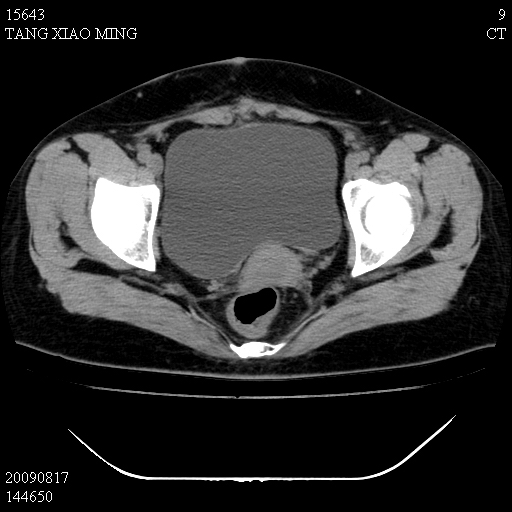

标题: CT21692:盆腔病变

女,33岁,右下腹痛2年余,既往宫外孕病史,如在我院手术,结果下周公布,

可能的诊断。1子宫内膜异位【子宫腺肌症并右卵巢巧克力囊肿】;2 右卵巢囊腺瘤。子宫肌瘤

1)考虑卵巢巧克力囊肿,不排除卵巢囊腺瘤。2)子宫肌瘤可能。

卵巢囊腺瘤,子宫肌瘤,直肠壁厚,不除外占位.